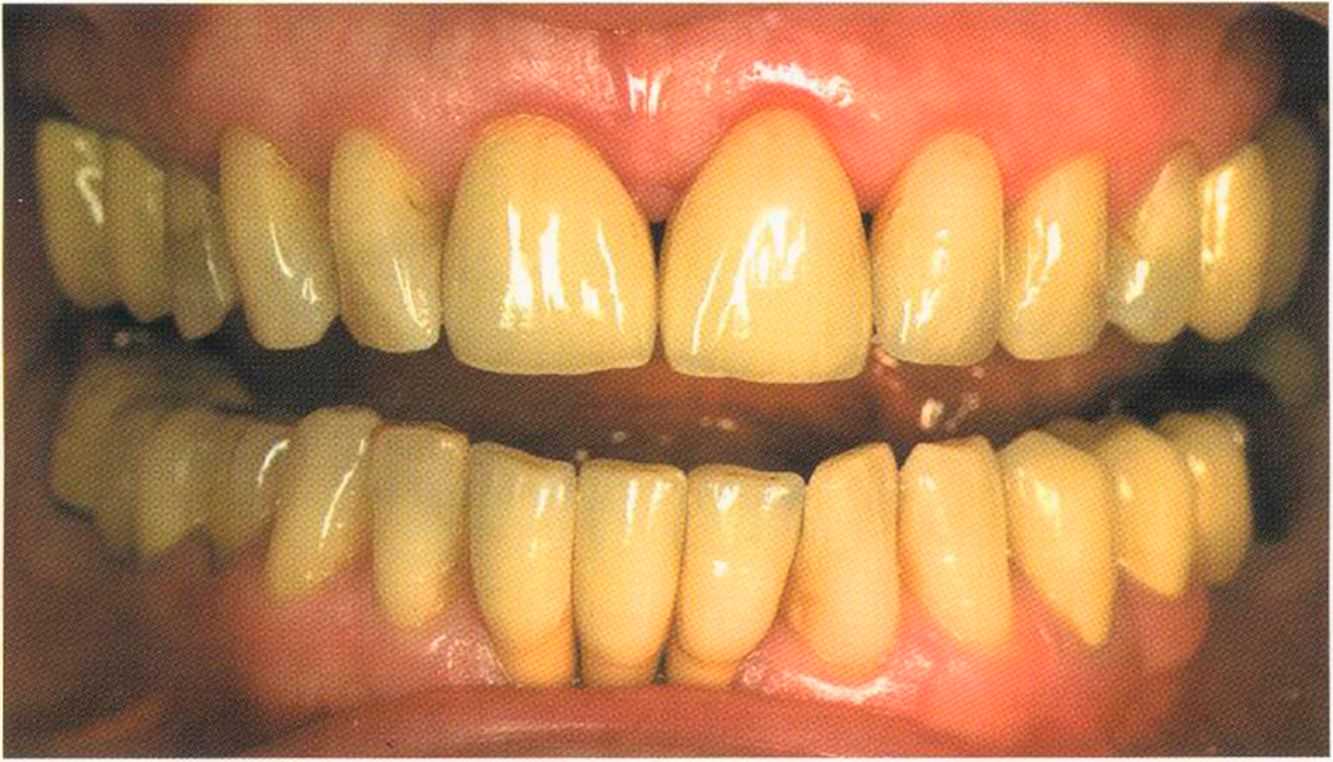

Эта женщина пришла в клинику доктора Лангханке с металлокерамической реставрацией.

Ей не нравились типичные в таких случаях темные края коронок и опаковость керамики.

Цвет 1М1 до 1М2 основной цвет в данном случае.